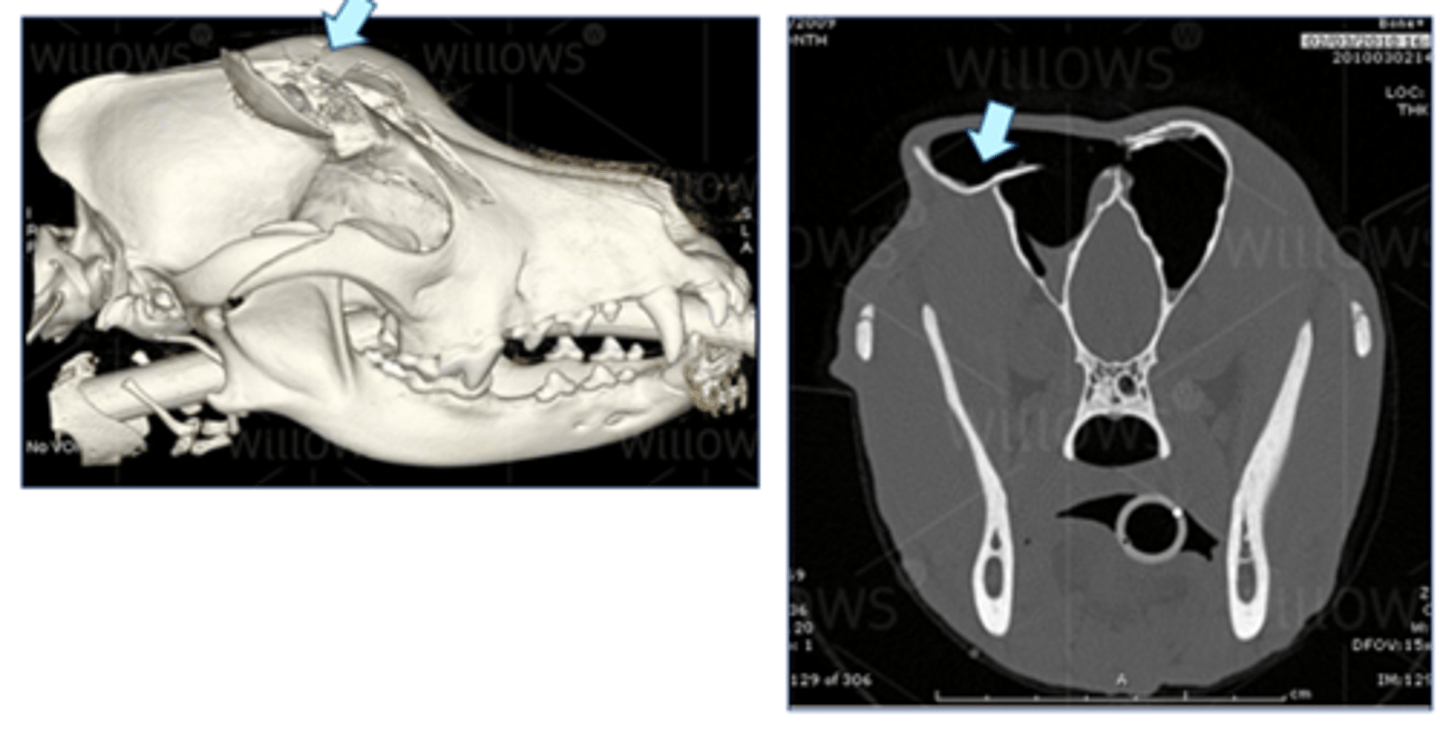

CT scan – skull fracture (dog kicked by horse)